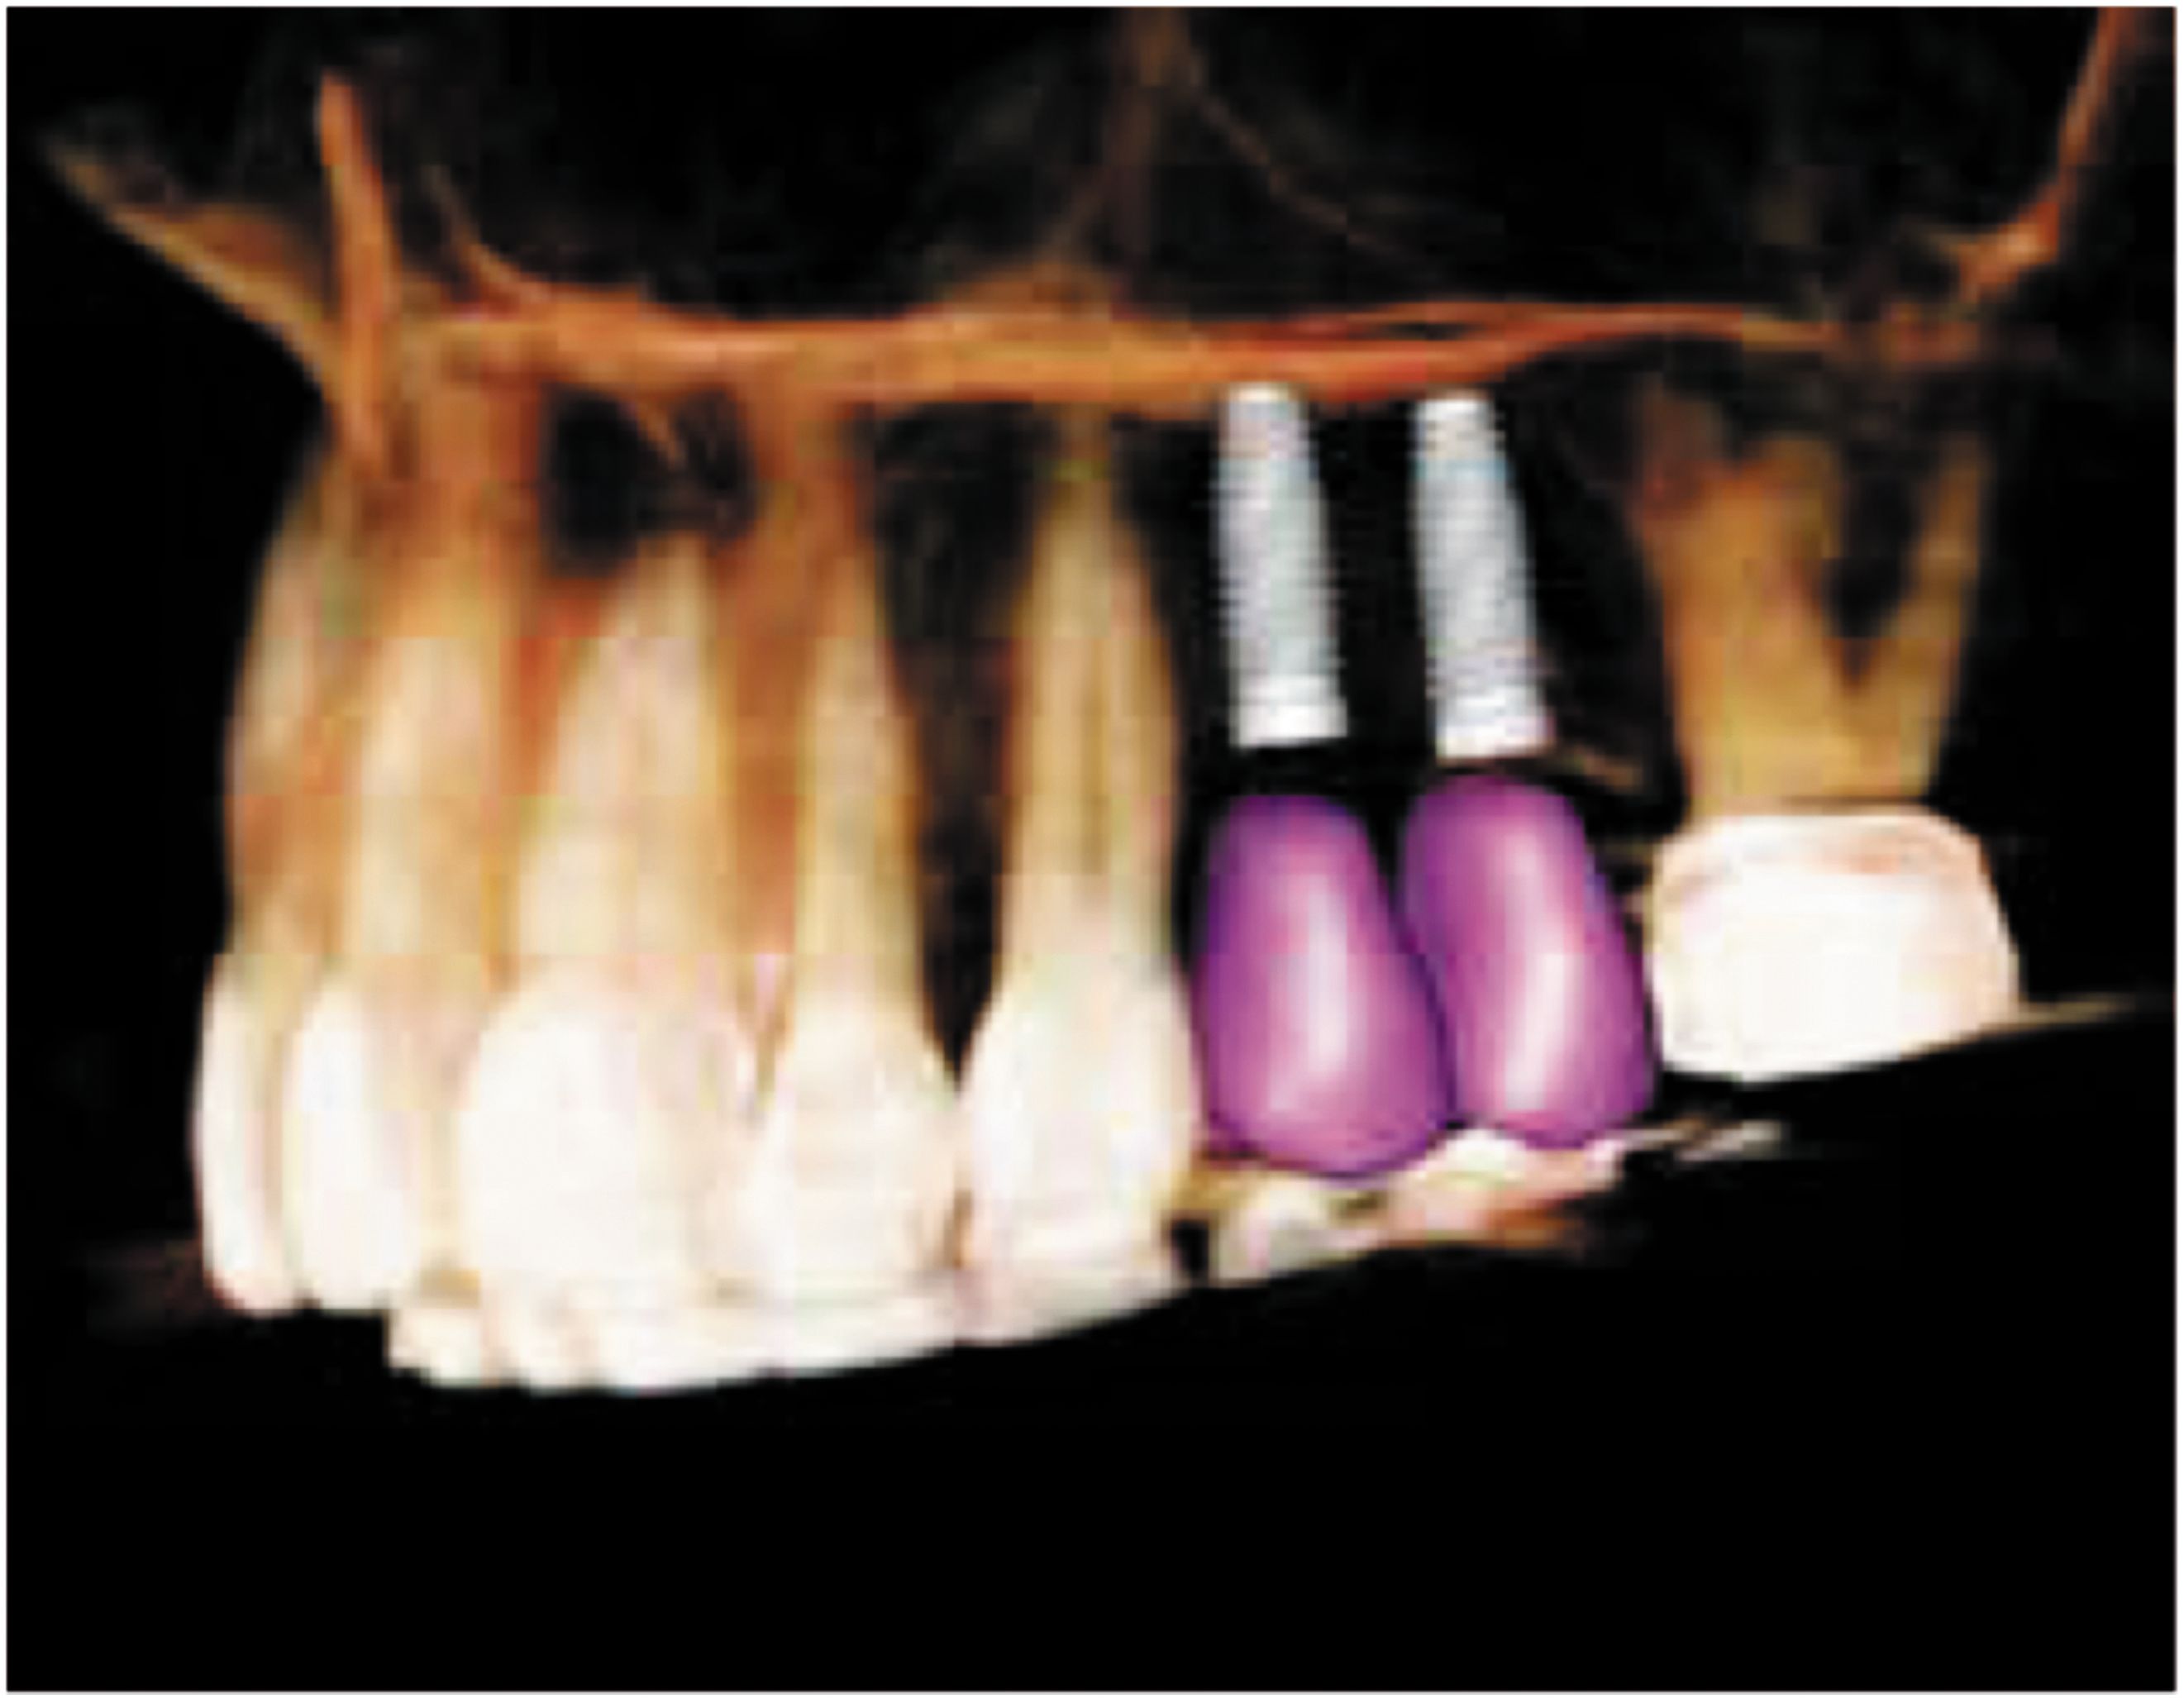

OP300 Maxio scans provide clinical-rich information to assist clinicians in the treatment planning process. The feature-rich 3D software enhances the data and gives you full control to design crowns, abutments and implants right from your Cone Beam 3D scan for fast, accurate treatment planning and predictable results. In just three simple steps, the software allows you to implant plan from the crown down:

1. OP300 Maxio software gives the ability to adjust and size the implant directly within the 3D rendering making the entire implant selection and positioning process a breeze.

2. Virtually add crowns from the restoration library and plan them within the 3D scan. With a few clicks of the mouse, you can also design your restoration to meet the functional requirements of your treatment plan.

3. Complete the design by adding the abutment and make any final adjustments quickly and accurately. This will allow you to refine and verify the implant selection and placement in respect to the restoration.

Once your design is complete, just select to transfer the case to the cloud server to have high-quality surgical guides made by Anatomage. With a fast turnaround, the guides will be produced in California at a flat fee independent from the number of implants or the complexity of the design.